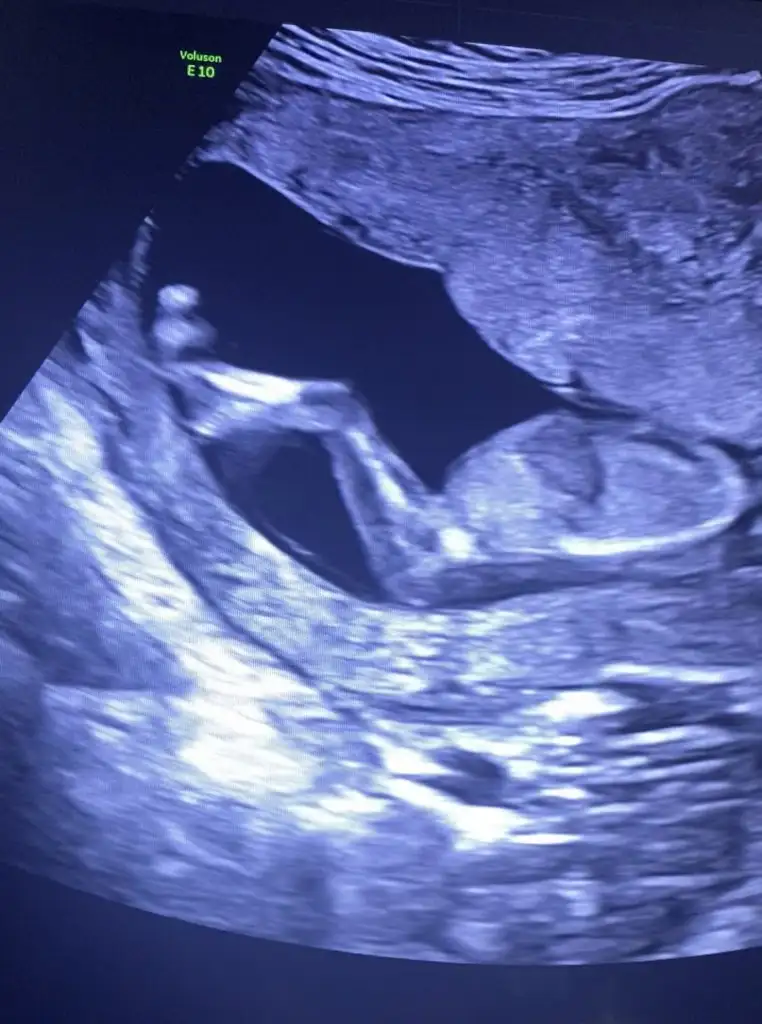

7 haftada odamı vajinal bakıldı vajinal ise erkekIkra meyra banada kesenden tahminde bulunabilir misin. Vajinal bakıldı ilki 6. Hafta ikincisi 7. Hafta.Biliyorum çok erken ama tecrübelerine dayanarak tahminde bulunursan sevinirim.

Evet ikiside vajinal7 haftada odamı vajinal bakıldı vajinal ise erkek

Ben 6 hafta vajinal sandımEvet ikiside vajinal

Erkek diyorumIkra meyra banana tahmin yapabilir misiniz?14 haftalık ultrasonŞimdiden teşekkür